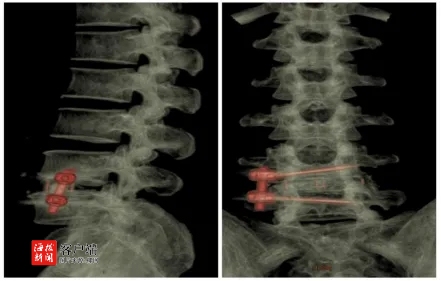

手术当天,李奶奶在医护人员的陪伴下,被缓缓推进了手术室。孟教授和他的团队,以专业、精准的操作,开始了这场精细的手术。在计算机导航的辅助下,他们小心翼翼地避开了重要的血管和神经,尽量减少对周围组织的损伤。时间一分一秒地过去,手术室内充满了专注和紧张的气息。经过一个小时的精心操作,手术终于顺利完成,孟教授走出手术室,向焦急等待的李奶奶家人传达了手术成功的好消息,这让李奶奶家人心中的石头终于落地。

李奶奶低头看着自己的手术伤口,那是一道约4厘米长的细小痕迹,这微小的伤口,见证了一场无声的奇迹,是孟教授和他的团队精湛技艺的证明。